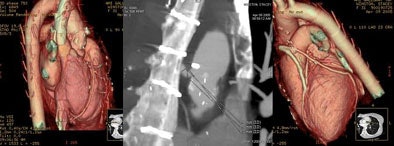

![]() |

| A 59-year-old woman presenting with chest pain had a normal CTA, as shown below right with visualization of the atrioventricular nodal branch. |